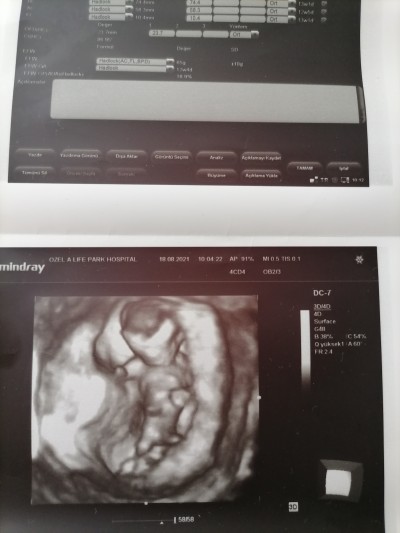

Cinsiyet tahmini yapabilir misiniz

14+0

Tamamen atıyorum erkek gbi geldi :)

Erkek olabilir =) aslında tahminde bulunmuştur baya net görünüyor bebek

Yan duruyor göremiyorum dedi

Kız bu :) sağlıkla gelsin minnak